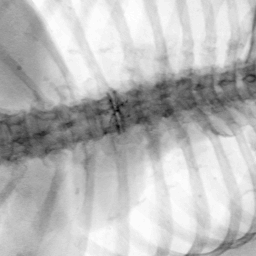

Exp. 3: Adult thorax data: To show the versatility of our approach we also apply it to adult thorax scans. For this experiment no organ specific training is performed but the whole volume is used. We evaluate reconstruction performance similar to Exp. 1 and Ti^^subscript𝑇𝑖\hat{T_{i}} prediction performance when ΩΩ\Omega is projected on an external plane, comparable to X-Ray examination using C-Arms. The latter provides insights about our method’s performance when applied to interventional settings in contrast to motion compensation problems. 60 healthy adult thorax scans were randomly selected, 51 scans used for ΩtrainsubscriptΩ𝑡𝑟𝑎𝑖𝑛\Omega_{train} and nine scans used for ΩvalidationsubscriptΩ𝑣𝑎𝑙𝑖𝑑𝑎𝑡𝑖𝑜𝑛\Omega_{validation}. Each scan is intensity normalised and resampled in a volume of 200×200×200200200200200\times 200\times 200 with spacing 1mm×1mm×1mm1𝑚𝑚1𝑚𝑚1𝑚𝑚1mm\times 1mm\times 1mm. Using the Fibonacci sampling method, 25 sampling plane of size 200×200200200200\times 200, evenly spaced between -50 and +50, were rotated over 500 normals. Training took approximately 20 hours for 60 epochs. Fig. 4c shows an example reconstruction result gaining 28dB PSNR with additional SVR. Ti^^subscript𝑇𝑖\hat{T_{i}} prediction takes approx. 20 ms/slice for this data.

Figure 4: (a): Comparison of a single slice from raw low-dose thorax CT data; (b): reconstruction based on SVRNet Ti^^subscript𝑇𝑖\hat{T_{i}} regression; (c): SVR initialized with SVRNet transformations after four iterations of SVR; (d): PSNR of (b) and (c) compared to (a). (e): shows a projection of an unseen pathological test CT volume as DRR and (e) shows a DRR at the location predicted by our method when presented with the image data in (e).

We use Siddon-Jacobs ray tracing [15] to generate Digitally Reconstructed Radiographs (DRRs) from the above described data. For training, we equally sample DRRs on equidistant half-spheres around 51 CT volumes at distances of 80cm, 60cm, and 40cm, between 90superscript90-90^{\circ} and 90superscript9090^{\circ} around all three co-ordinate axes. For validation, we generate 1000 DRRs with random rotation parameters within the bounds of the training data at 60cm distance from the volumetric iso-centre. We trained on healthy volunteer data and tested on nine healthy and ten randomly selected pathological volumes (eight lung cancer and two spinal pathologies). Our approach is able to predict DRR transformations relative to the trained reference co-ordinate system with an average translation error of 106mm and 5.6superscript5.65.6^{\circ} plane rotation for healthy patients, and 130mm and 7.0superscript7.07.0^{\circ} average error for pathological patients. An example is shown in Fig. 4e,f. Note that these values are good enough to robustly initialize intensity-based registration refinement. SVRNet prediction can be improved by generating a denser training data set, in particular, in more equidistant half-spheres.